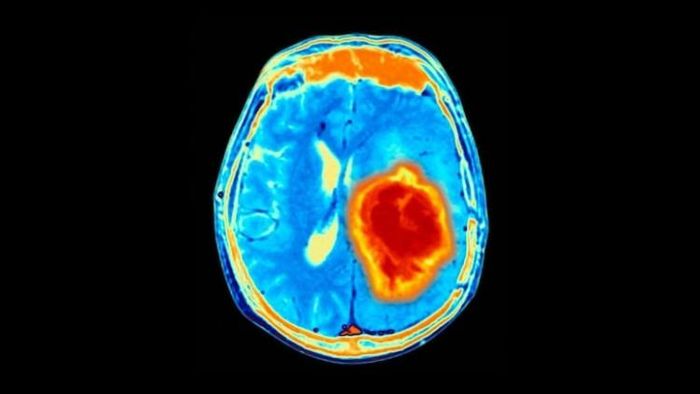

ডিমেনশিয়া নিজে শুধু একটি রোগ নয়। পরিবর্তে, এটি রোগের একটি গোষ্ঠী, যা আলঝাইমার রোগ সহ বিভিন্ন নির্দিষ্ট রোগের সঙ্গে ওতপ্রোতভাবে জড়িত। অ্যালঝাইমার অ্যাসোসিয়েশনের মতে, সাধারণ "ডিমেনশিয়া" এবং তার অধীনে থাকা রোগগুলি মস্তিষ্কের অস্বাভাবিক পরিবর্তনের কারণে হয়। যাতে চিন্তার ক্ষমতা হ্রাস পায়। যা দৈনন্দিন জীবন এবং স্বাধীন কাজকর্মের ক্ষমতাকে নষ্ট করে দেয়।

তাঁরা দেখেছেন যে, মধ্যবয়সী ব্যক্তিরা যাঁরা সপ্তাহে অন্তত একবার খারাপ স্বপ্ন দেখেন, তাঁদের পরবর্তী দশ বছরে বুদ্ধিহ্রাসের সম্ভাবনা প্রায় চার গুণ বেশি তাঁদের চেয়ে, যাঁরা খুব কমই দুঃস্বপ্ন দেখেন। খারাপ স্বপ্ন ঘুমের খারাপ মানের ফলাফল হতে পারে, যা ডিমেনশিয়ার দিকে মস্তিষ্ককে নিয়ে যেতে পারে।